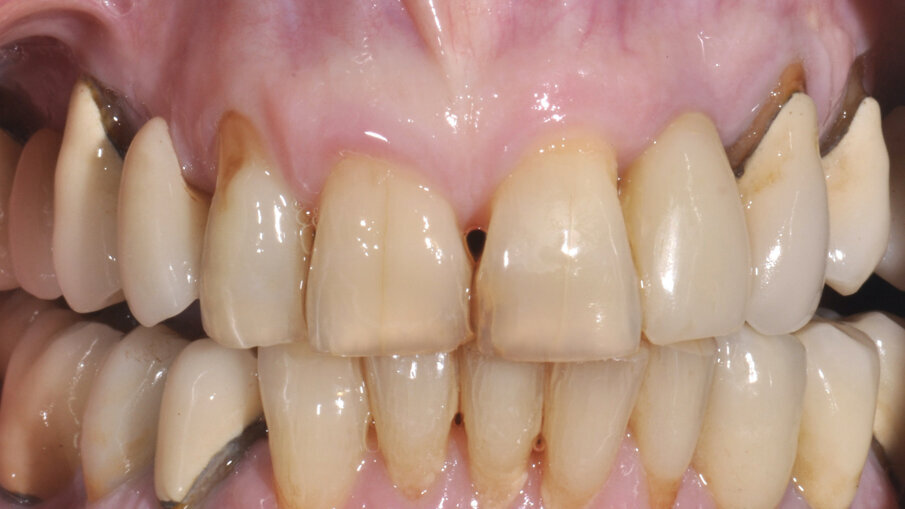

A 7 giorni è stato eseguito un controllo per verificare lo stato dei tessuti gengivali e continuare a motivare la paziente riguardo all’esclusione dai carichi masticatori (Fig. 9). A 90 giorni è stato rimosso il provvisorio per procedere al restauro ceramico. Nonostante la superficie SLActive preveda un accorciamento dei tempi di integrazione, è stato deciso un tempo di attesa convenzionale per accertarsi della stabilità dei tessuti molli perimplantari (Figg. 10-12). È stato eseguito un workflow digitale a partire dall’impronta ottica, fino alla realizzazione di un restauro in Zirconia precolorata e stratificata vestibolare (Dental Direkt 1200 e Creation ZI-CT) su base titanio (Figg. 13, 14). Il restauro è stato consegnato mediante avvitamento a controllo di torque secondo le indicazioni della casa produttrice (Figg. 15, 16).

Fig. 10_Aspetto clinico a 90 giorni.

Fig. 11_Condizionamento dei tessuti molli.

Fig. 12_Confronto tra la situazione iniziale, quella post-chirurgica e quella al termine del periodo provvisorio.